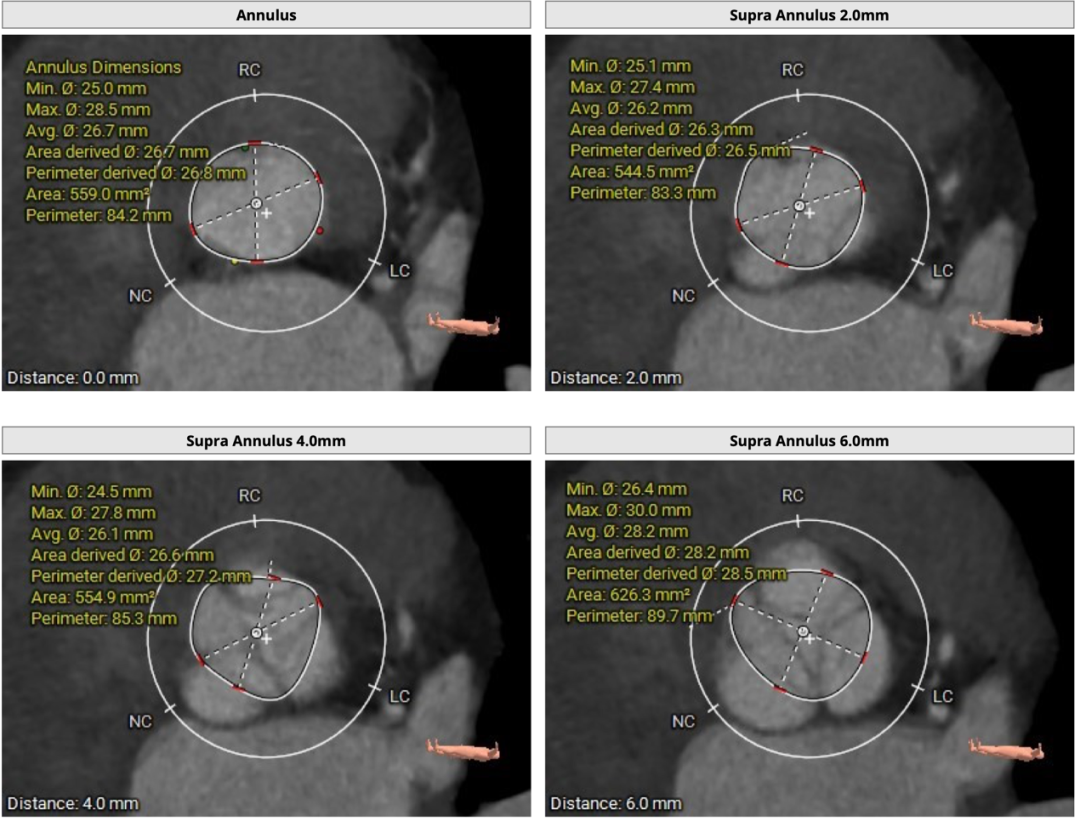

CT分析

患者主动脉瓣三叶式,瓣叶基本等大,瓣叶不厚,瓣叶未见明显钙化;主动脉瓣环周长折算直径约26.8mm:

双侧冠脉开口高度可,LCA 13.2mm,RCA 20.6mm: